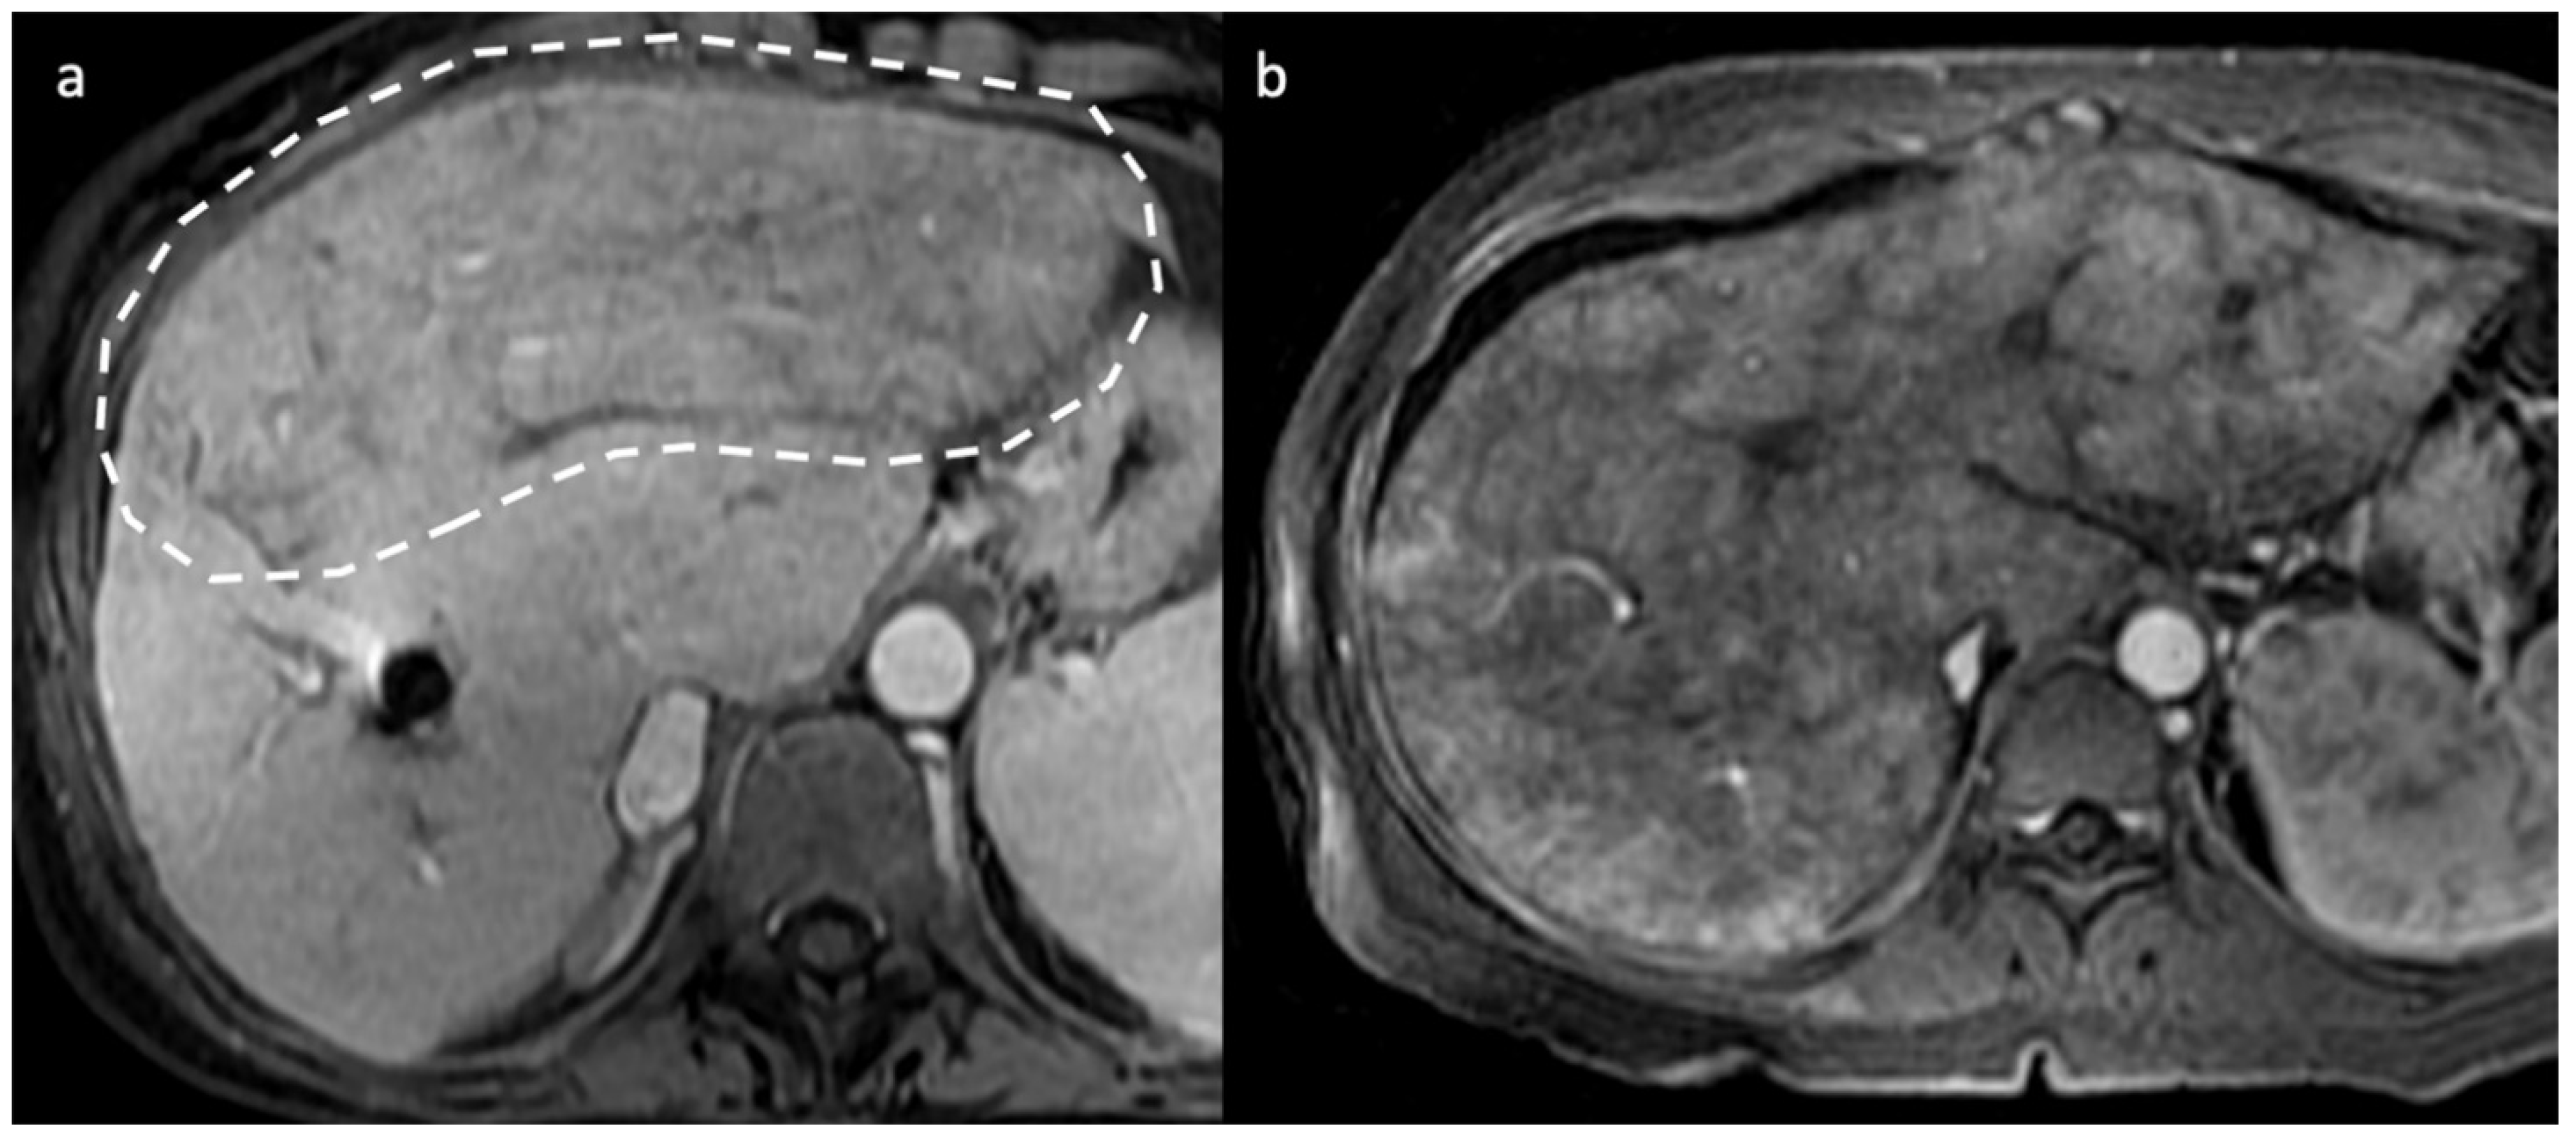

- Indirect signs: non-specific. They represent the consequences of long-standing hepatic venous impairment, including liver parenchymal changes with fibrosis and atrophy of involved segments and hypertrophy of unaffected territories (e.g., caudate lobe hypertrophy). On CT and MRI, centrilobular or sinusoidal congestion, represented as heterogeneous ”mosaic” enhancement after contrast media is also characteristic. Other signs include ascites, portal hypertension, and the presence of benign regenerative nodules, as well as hepatocellular carcinoma [6].

3.2. Computed Tomography and Magnetic Resonance: What to Look For

- Mamone, G.; Miraglia, R. The “mosaic pattern” in hepatic sinusoidal dilatation. Abdom. Radiol. 2019, 44, 2949–2950. [Google Scholar] [CrossRef]